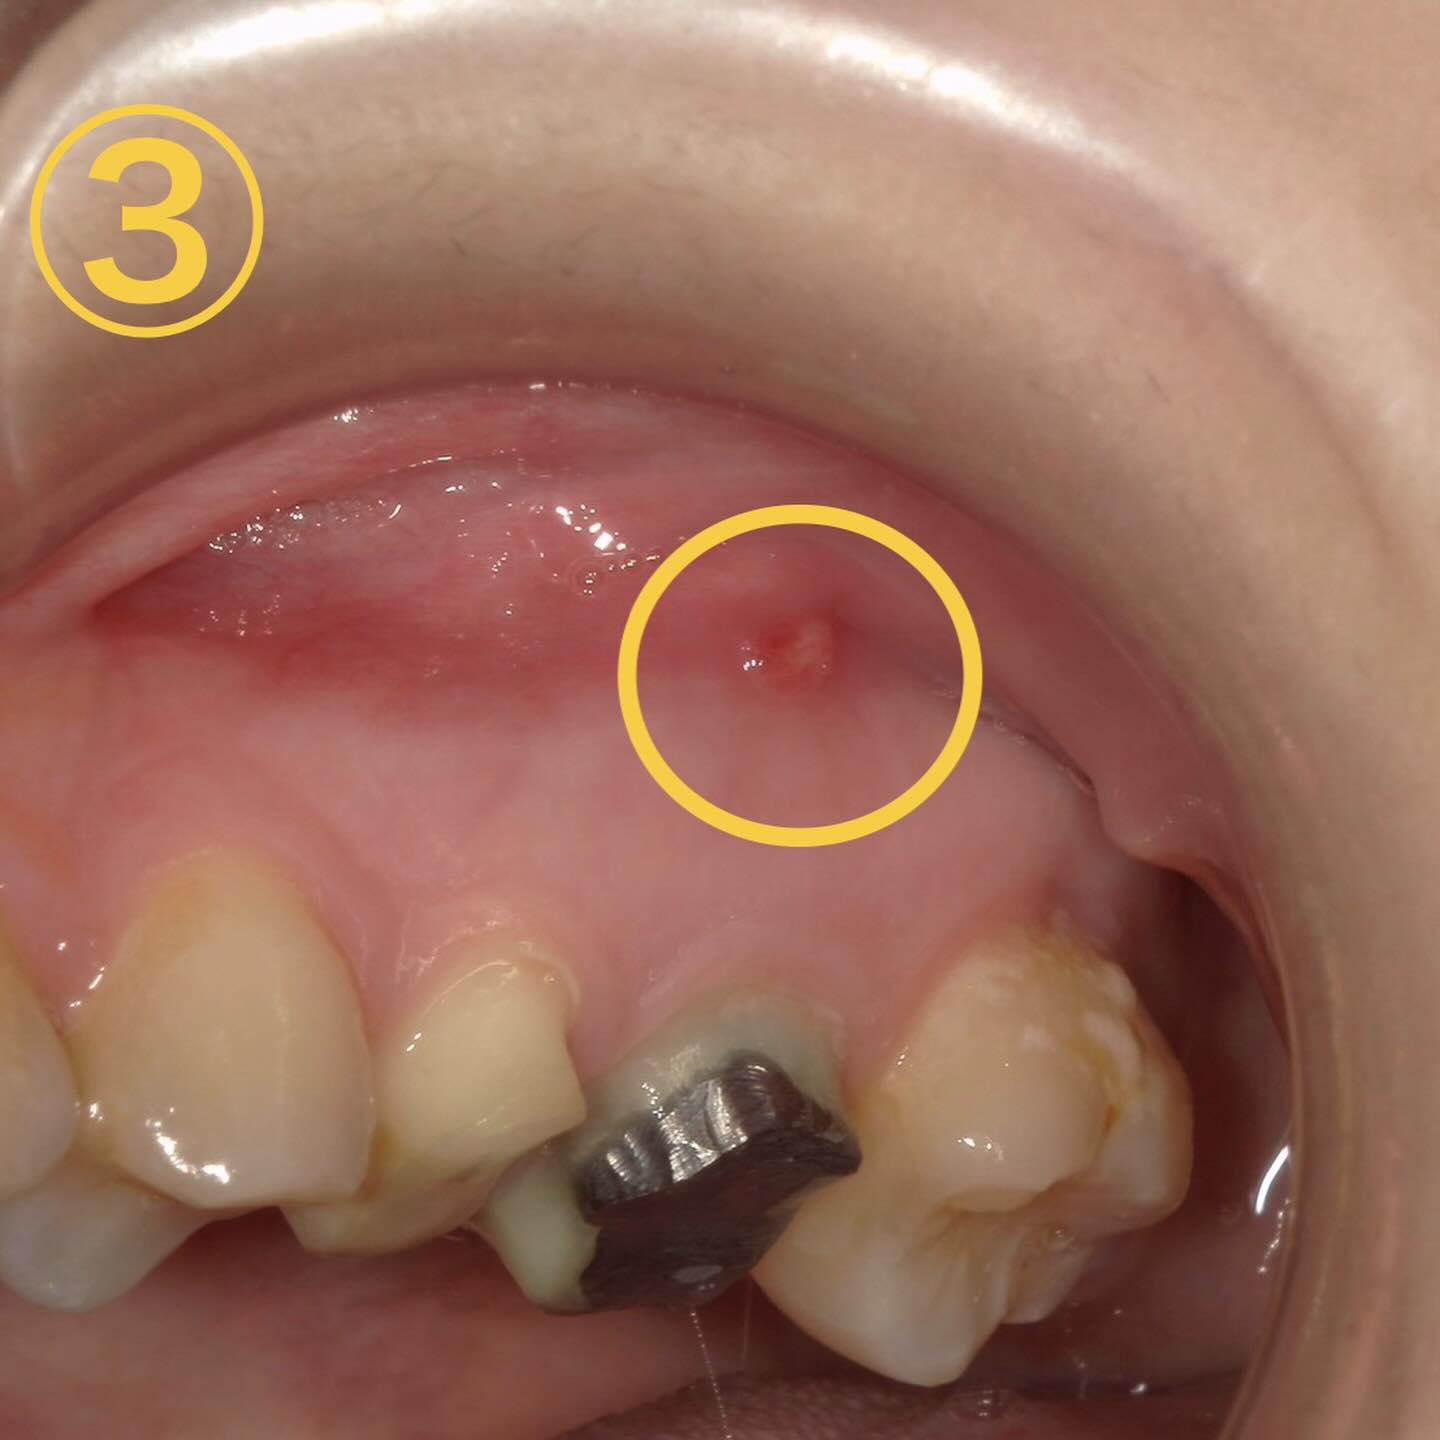

次に画像③に行きます

これは口内炎ではありません🙅♀️

根尖病巣から発生するフィステルという膿の排膿路のことを言います✍️

特徴→・昔治療した歯の近くに出来る事が多い・痛みは無い事が多い・数日で消えるがまた再発する

💊治療法→再度根の治療(根管治療)を行う